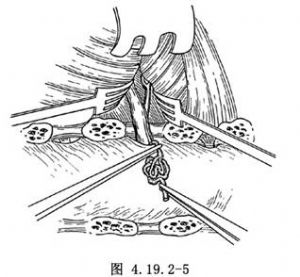

3.將硬脊膜表面的畸形血管團加以電凝並予以切除(圖4.19.2-5)。